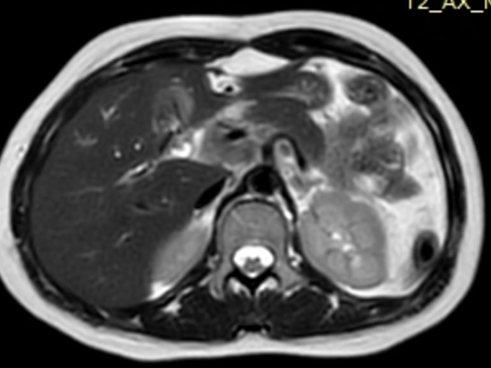

On follow-up, the patient presented with features of obstructive jaundice; therefore, she was re-admitted and underwent MRCP followed by triphasic CT scan. As demonstrated by (Figure 3). The MRCP report revealed upper abdominal lymphadenopathy with a mass effect on the CBD, leading to cholestasis and altered signal intensity in segment IV of liver has left lobe.

Figure 3: Bulky lymphadenopathy producing mass effect on the common bile duct, leading to obstructive cholestasis and secondary signal changes in segment IV of the left hepatic lobe.